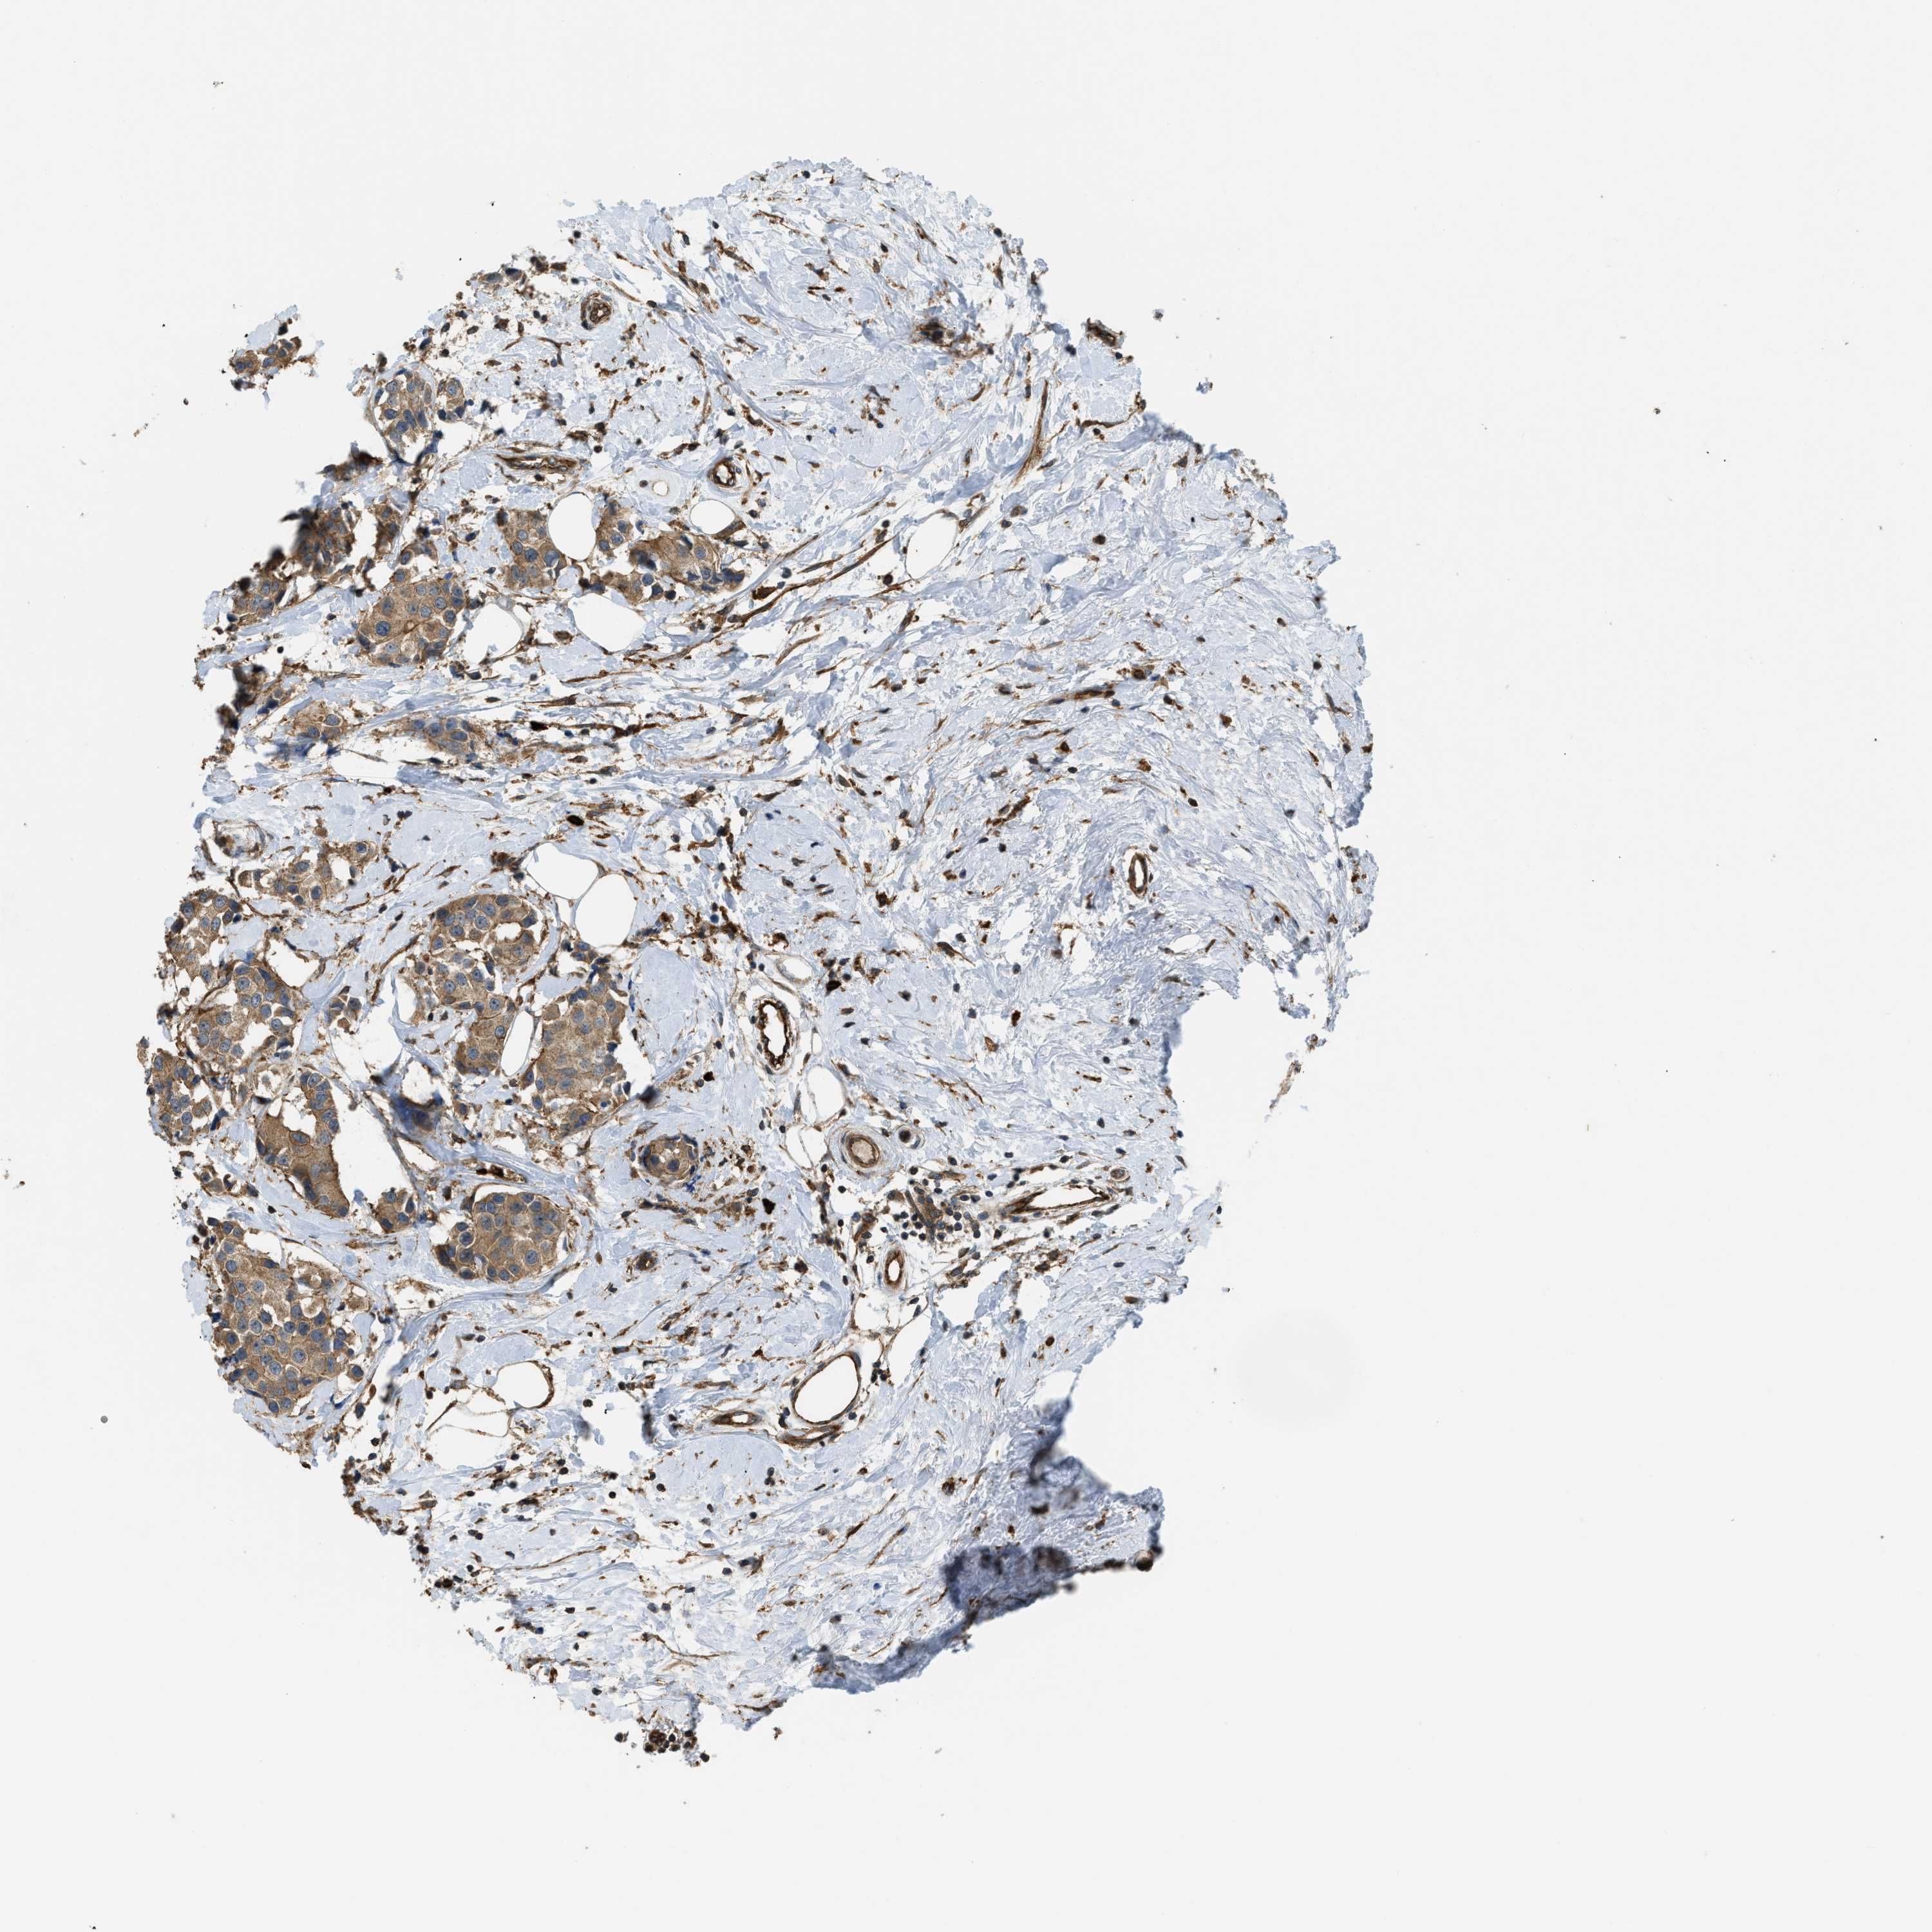

CANCER BREAST CANCER Show tissue menu

BRCA TCGA BRCA VALIDATION PROTEIN EXPRESSION

ANTIBODIES

AND

VALIDATION